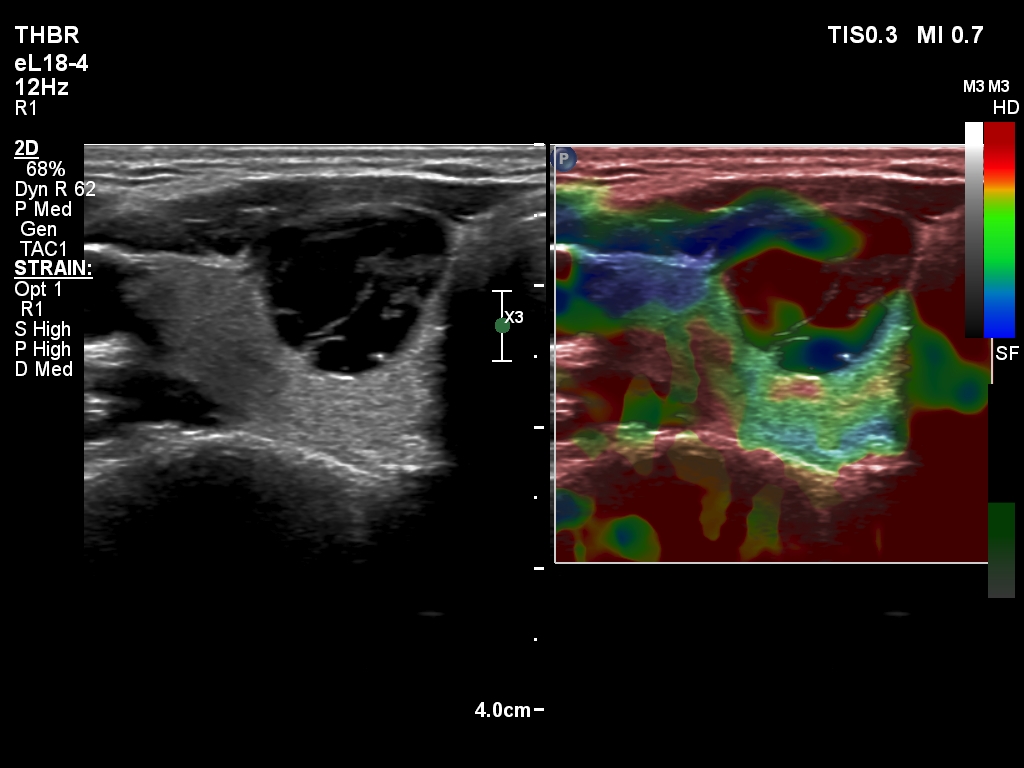

Ultrasonography. The thyroid was echonormal. There was a cystic nodule in the right lobe. The lesion had spongiform portions. The nodules presented all three possible signs of an extrathyroidal extension. There was a minimally hypoechoic nodule in the left lobe.

- The categorization of the cystic nodule depends on the definition of spongiform nodules: the spongiform areas exceeded 50% but the nodule was not entirely spongiform.

- Great proportion of benign nodule presents signs of a possible extrathyroidal extension because these features are non-specific, this is particularly true for cystic nodules located at the edge of a lobe. The liquid produced often bulges the surface of the thyroid. The contour of this nodule was abutting and bulging and the thyroid capsule was discontinuous.